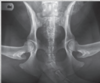

Review pelvic anatomy.

66

Extended VD pelvis view means..

the patellas are also in the image and they're rotated to position in the center of the femurs.